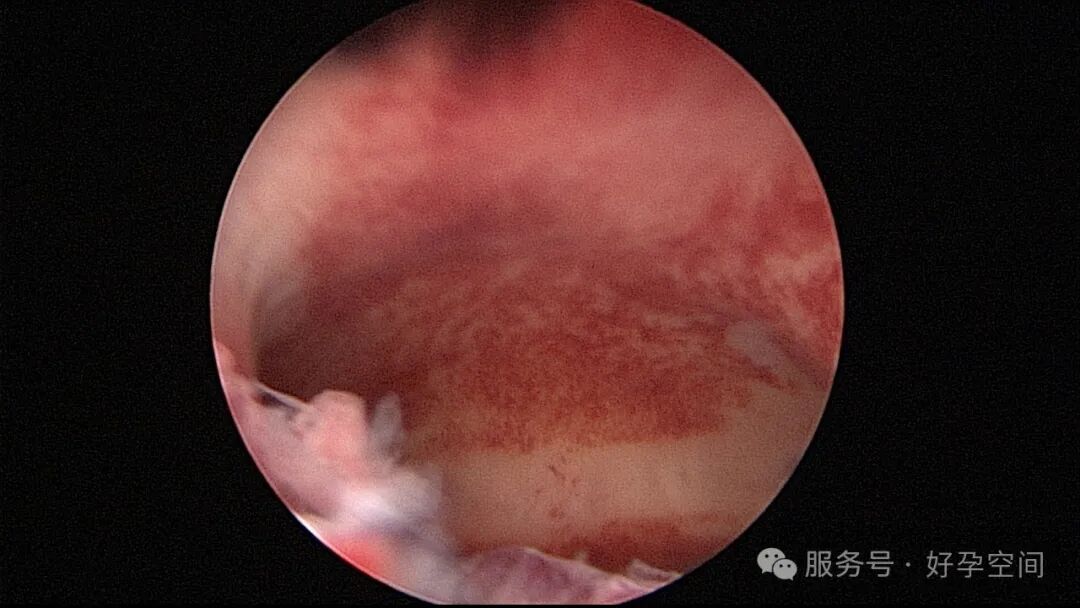

输卵管吻合术后妊娠,稽留流产,清宫术后宫腔粘连,宫腔镜单极电针分粘

分粘后宫腔镜二探,残留少许膜性粘连,镜鞘分粘